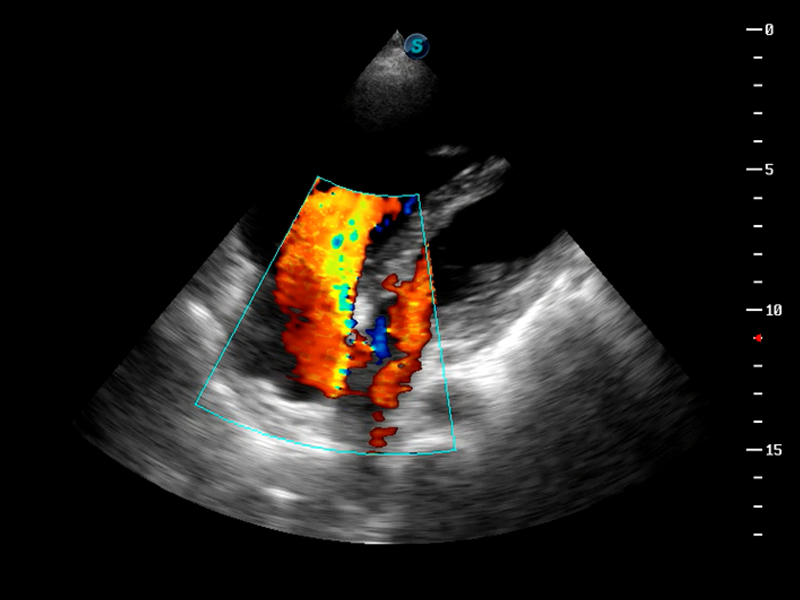

S9便携式彩色多普勒超声诊断仪是哈哈体育官网研发的高端便携彩超设备,外观设计新颖、产品性能卓越。S9在便携超声领域采用了突破传统的触摸屏交互设计,并以先进的软件硬件技术和设计理念,为您带来清晰的图像质量、稳定的工作性能和便捷的操作体验。

AutoC智能血流追踪